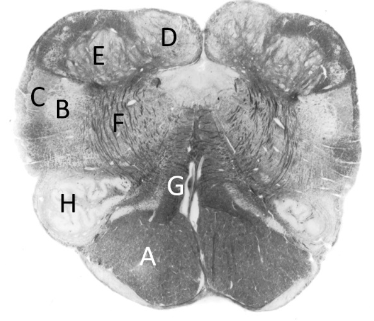

at what level is this?

spino-medullary junction

what is a?

spinal trigeminal nucleus

what is b?

nucleus cuneatus (sm)

what is c?

fasciculus gracilis (sm)

what is e?

pyramidal decussation

what is f?

spinocerebellar & (more medial) spinothalamic tract